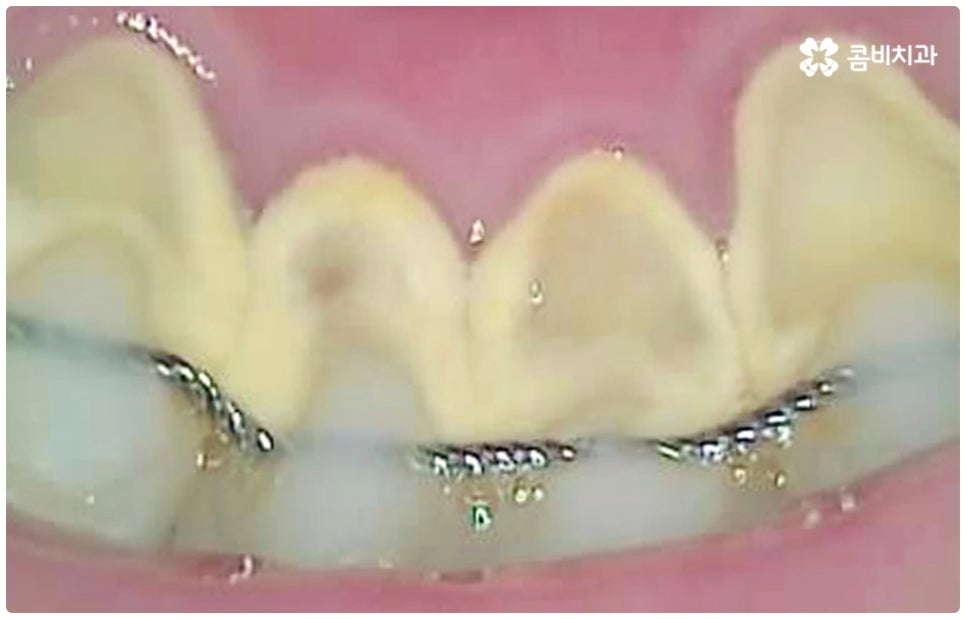

교정을 하고 있거나 사후 유지 장치를 부착한 경우, 보철물 치료를 받은지 오랜 시간이 지나 보철물과 치아 사이 틈이 생겼거나 잇몸 질환 및 치경부 마모증 등으로 인해 치근이 드러난 경우에는 더욱 치석이 빨리 쌓이고 충치 역시 쉽게 발생할 가능성이 높아지므로 스케일링 치료에 좀 더 신경 쓰는 게 좋을 거예요. 일반적으로 성인의 경우 1년에 한 번 또는 두 번 정도 스케일링 치료를 받는 것이 보통이지만, 이와 같이 좀 더 주의가 필요한 상황이라면 1년에 3~4번 정도로 주기를 짧게 하실 필요가 있어요. 1년에 한 번은 건강 보험을 통해 보다 합리적인 가격으로 스케일링 치료를 받으실 수 있으니 만약 이용해 보신 적이 없으시다면 올해가 가기 전에 관리 및 검진을 위해 치과에 내원해 보시길 권유드리고 있습니다.